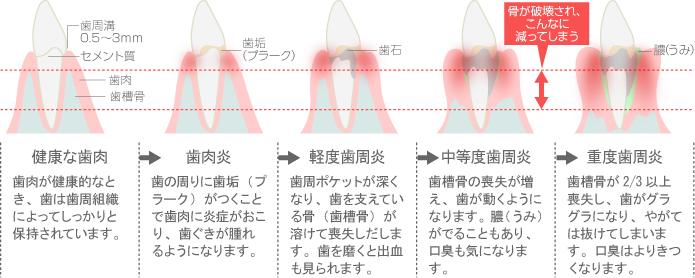

日本の成人8割が発症

歯周病とは、歯と歯を支える歯周組織におけるさまざまな病気の総称です。

歯と歯ぐきの間にたまった歯垢や歯石の中にある歯周病菌が歯ぐきにダメージを与え、少しずつ歯を支える組織を破壊して、最悪の場合は歯を失うことになってしまう恐ろしい病気です。

また、歯周病は「サイレントディシーズ(静かなる病気)」とも呼ばれ、痛みなどの自覚症状がほとんどなく進むため、気づかないうちに進行していることもあるので注意が必要です。

歯周病の進行状況を正確に把握し、その症状に合わせた最適な治療を行います。

軽度の場合は正しいセルフケアや歯石除去などを行って改善できることもありますが、重度の場合は外科治療が必要になることもあります。